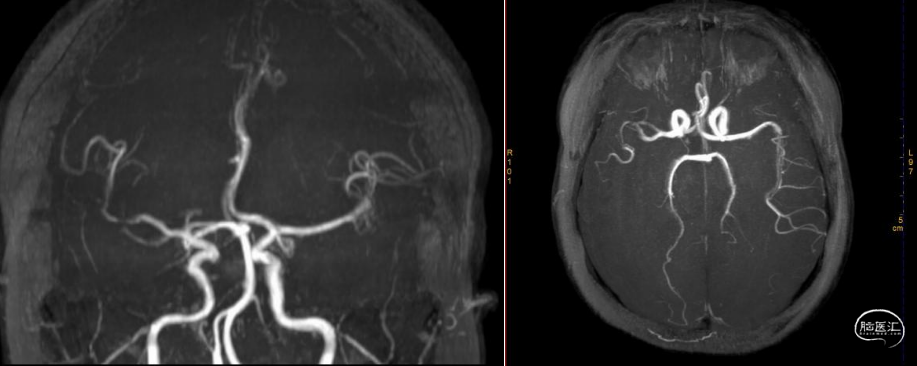

术前MRA显示右侧大脑中动脉远端变窄并分支稀疏。

患者女性,46岁,急性起病,发病时间明确,既往无特殊病史,颅脑CT排除脑出血,入院时距离发病不超过4.5小时,符合静脉溶栓适应症。溶栓后颅脑CT提示右侧大脑中动脉远端致密征,右外侧裂池变窄,同见“岛带征”,MRA见右侧大脑中动脉远端变窄并分支稀疏,狭窄或闭塞可能性大,ASPECT-CT评分10分,发病前mRS评分0分,NIHSS评分17分,有明确的取栓手术指征,定位右侧大脑半球,定性急性缺血性脑梗死,病因考虑动脉粥样粥样性脑梗死,心源性不排外。患者经静脉溶栓治疗后,MRA提示右侧大脑中动脉存在狭窄或闭塞,予急诊手术取栓治疗。